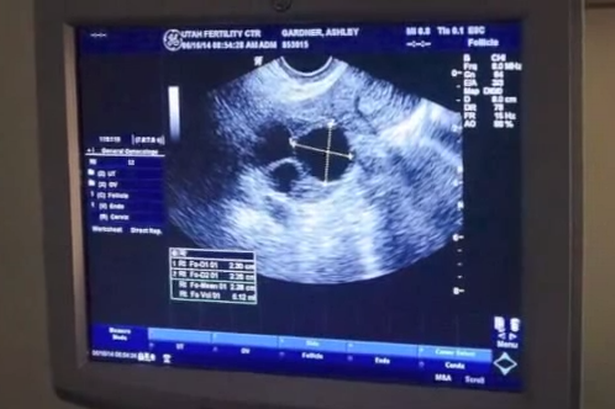

Tháng 7/2014, sau khi gom góp đủ tiền, hai người bắt đầu thụ tinh ống nghiệm. Bác sĩ và vợ chồng Gardner rất kinh ngạc khi kết quả siêu âm cho thấy Ashley mang thai hai cặp song sinh cùng trứng, theo Mirror.

Alicia Hallcock, một người bạn của cả Ashley và Tyson, đã ghi hình phản ứng của hai vợ chồng khi họ biết tin vui. Đây là trường hợp cực hiếm, chỉ chiếm tỷ lệ 1/70 triệu ca mang thai. Trong video, Ashley và Tyson nói không nên lời. Căn phòng ngập tràn tiếng cười khi sản phụ khoe ảnh siêu âm 4 đứa bé.

| Ashley Gardner mang thai hai cặp song sinh cùng trứng, một trường hợp chỉ xảy ra một lần trong số 70 triệu ca mang thai. Ảnh: Mirror |